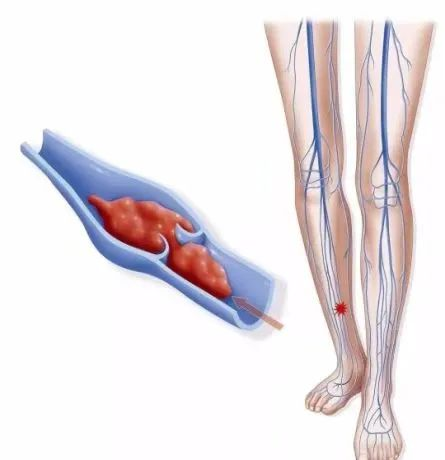

(3)四肢静脉疾病:如有手脚肿胀、疼痛、“蚯蚓样”包块等症状,疑为静脉血栓、静脉瓣功能不全引起。